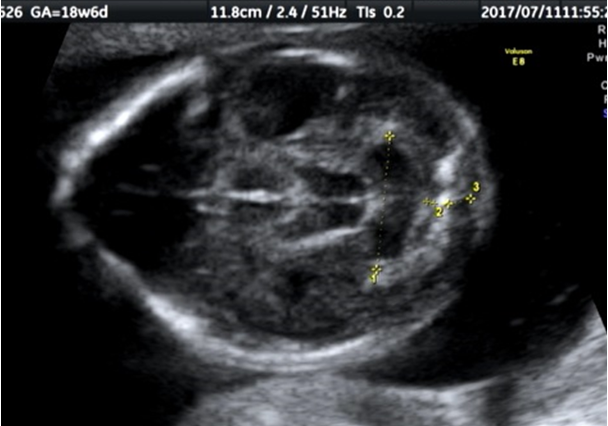

そして、バナナサインは、赤ちゃんの小脳が脊椎の方に落ち込んで、形がバナナのように見えるようになるので、その名前がつけられました。少し無理があるようにも思いますが。

それがレモンサインとバナナサインです。